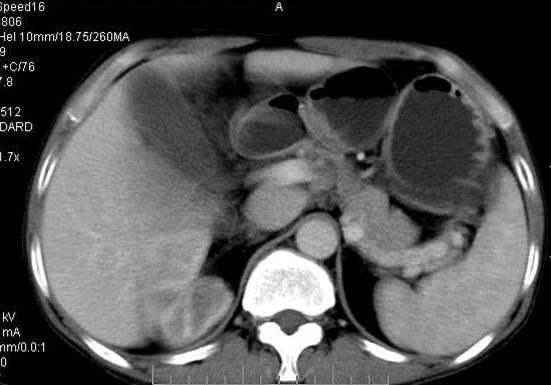

男性 60岁,腹部肿块4年余,肿块逐渐增大,活动性差,无血尿。

平扫

定位;肾明显与病灶杯口相交,可以肯定病变来自右肾。

定性;病灶囊性为主,前下部含实性成分,及钙化,部分壁厚薄不均。

肾囊实性病变有;1,囊性肾癌2,囊性肾瘤。3,复杂囊肿。4,重复肾伴积水。然2、3壁相对规则。

综上考虑;囊性肾癌》重复肾伴积水。